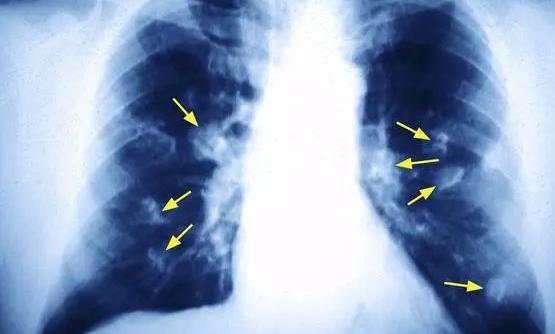

我国国家癌症中心的最新报告显示,肺癌是女性第二高发的癌症,仅次于乳腺癌。40-50岁女性中肺癌患者人数已经接近男性,达到了1:1的比例。但是国内女性的吸烟率很低,为何发生肺癌的概率却如此&ldqu……